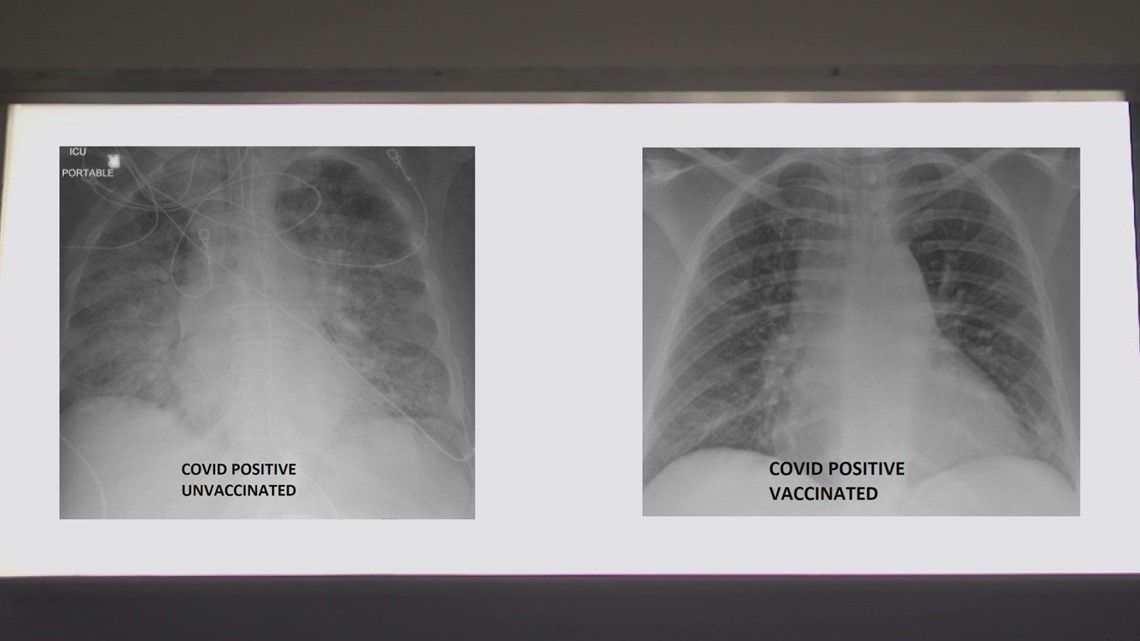

Për t’ua dëshmuar efikasitetin e vaksinës kundër COVID-19, mjeku ka publikuar rëntgenin e mushkërive të dy pacientëve me coronavirus – por që njëri prej tyre e ka marrë vaksinën, e tjetri jo.

Ai ka ekzaminuar rëntgenet dhe ngjyrën e bardhë në mushkëri që e tregon përhapjen e virusit, që sipas tij mund të jenë baktere, mukozë apo sekrecion.

“Nëse shikoni mushkëritë e pacientit të vaksinuar, do të shihni që ato janë plotë oksigjen dhe duken të zeza – apo më mirë thënë dominon ngjyra e zezë sesa e bardha, siç ishte rasti me pacientin me COVID-19 por që nuk është vaksinuar.